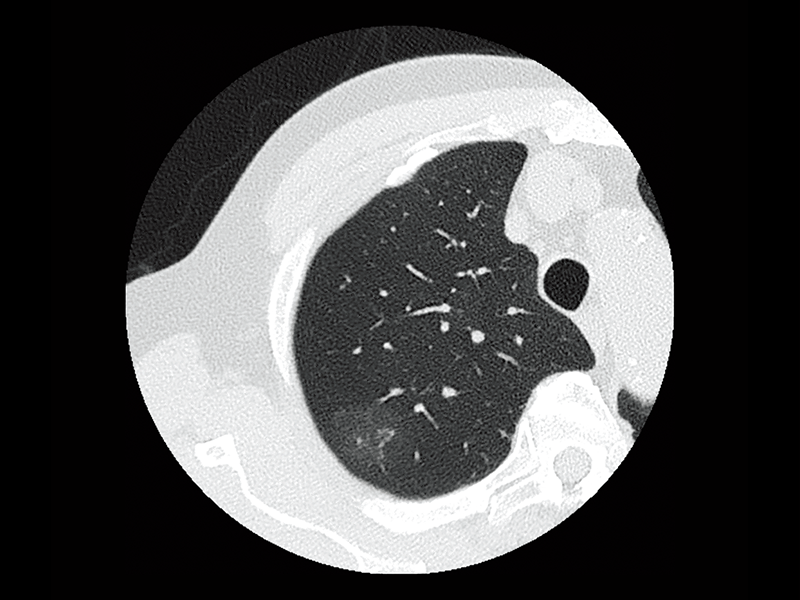

Non-tuberculous mycobacteria

Lung screening (CTDlvol: 2.0 mGy)